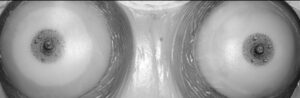

Reconstruction d’aréole mammaire en 3D

La pigmentation réparatrice de l’aréole mammaire permet de recréer visuellement une aréole naturelle après une chirurgie ou dans le cadre d’un parcours de reconstruction. Cette prestation est réalisée avec délicatesse, précision et respect, afin d’obtenir un rendu harmonieux et réaliste.

Tarif avec 1 retouche comprise: 380 € l’une, 600 € les 2